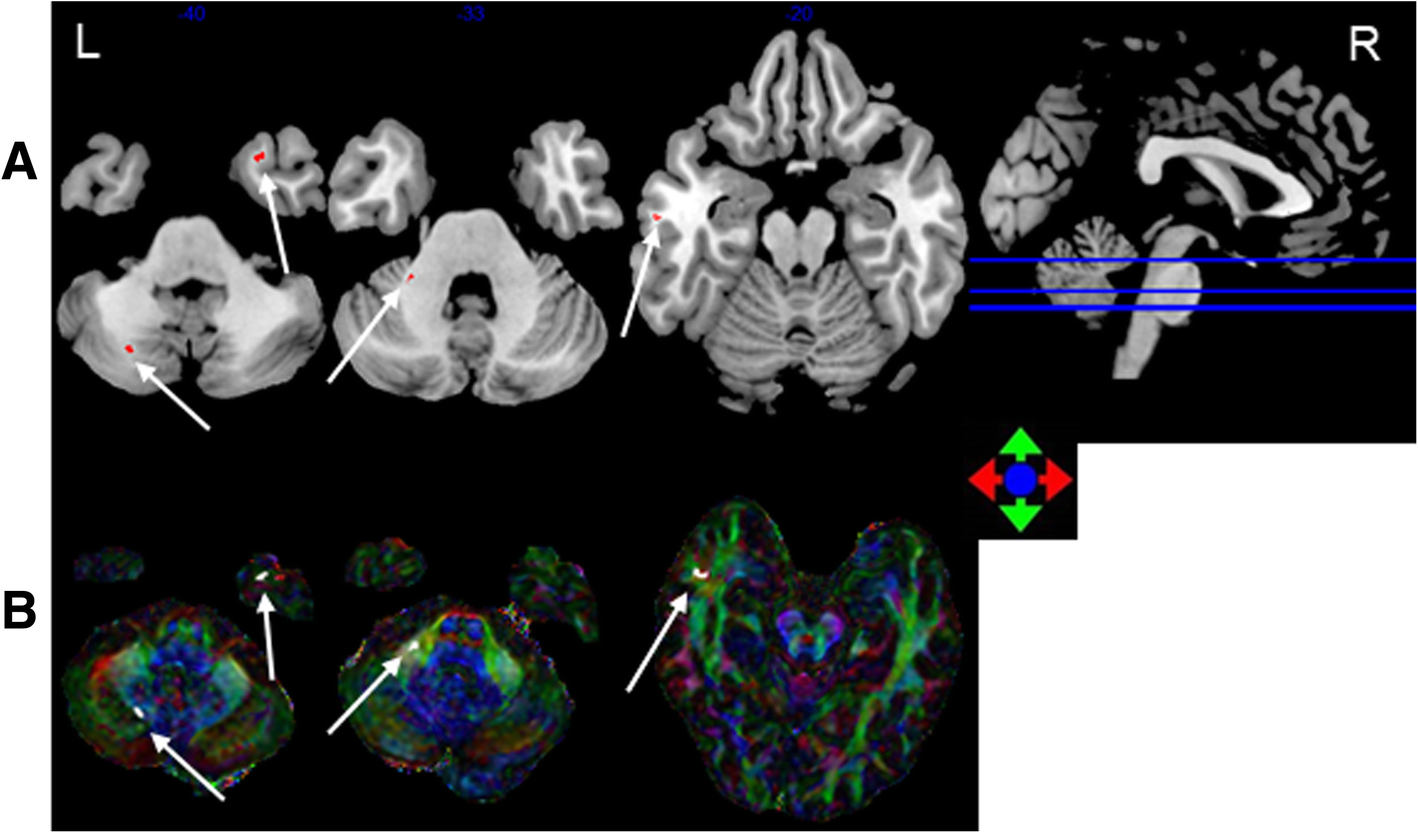

Fig. 3

The most discriminating voxels for the classification of > 12 months post-RT versus control; the image is the cutaway view: a displayed on the mean group fractional anisotropy (FA) map, the abnormal regions are shown in red; b FA map displayed in color (Red represents the left and right direction, green represents the up and down direction, and blue represents the front and rear direction). The left side of the brain is on the left side of the image. L = left, R = right